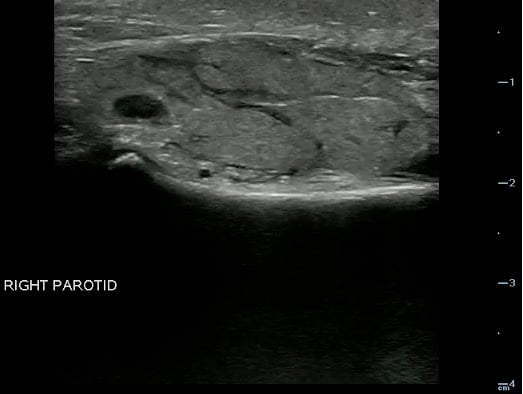

- The Parotid gland has intraglandular lymph nodes that are commonly seen within the parenchyma of the parotid gland.

- Figure 19 and 20. Parotid gland lymph nodes

Video 14. Parotid gland lymph nodes